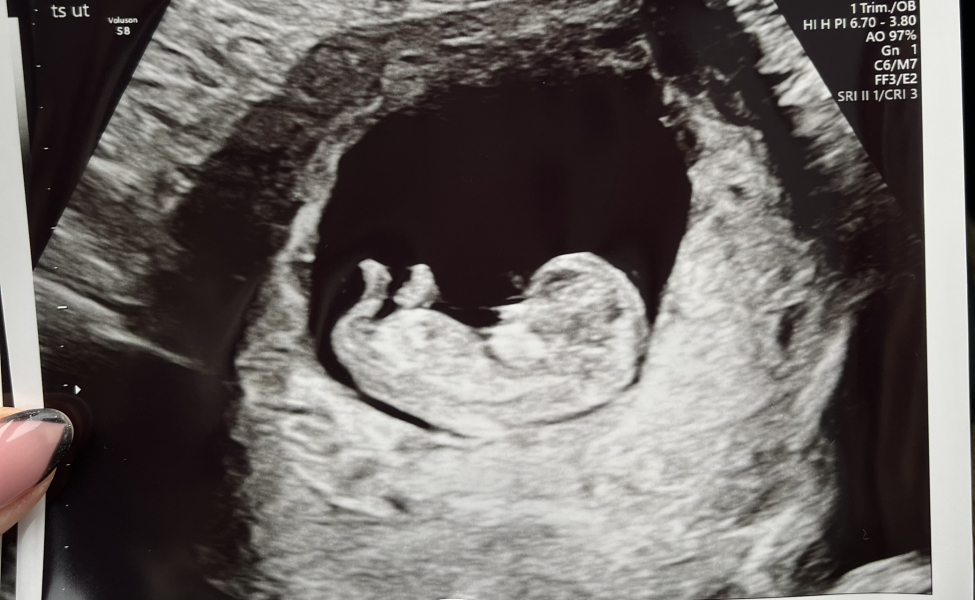

Today was so lovely! Baby measuring three days ahead ❤️

@Moosh18 amazing!! Look at that beautiful baby 😍 are you going to start telling family and friends?

@Moosh18 Congratulations, what a beautiful scan 😍❤️

@Moosh18 what a lovely scan, a proper wee baba!